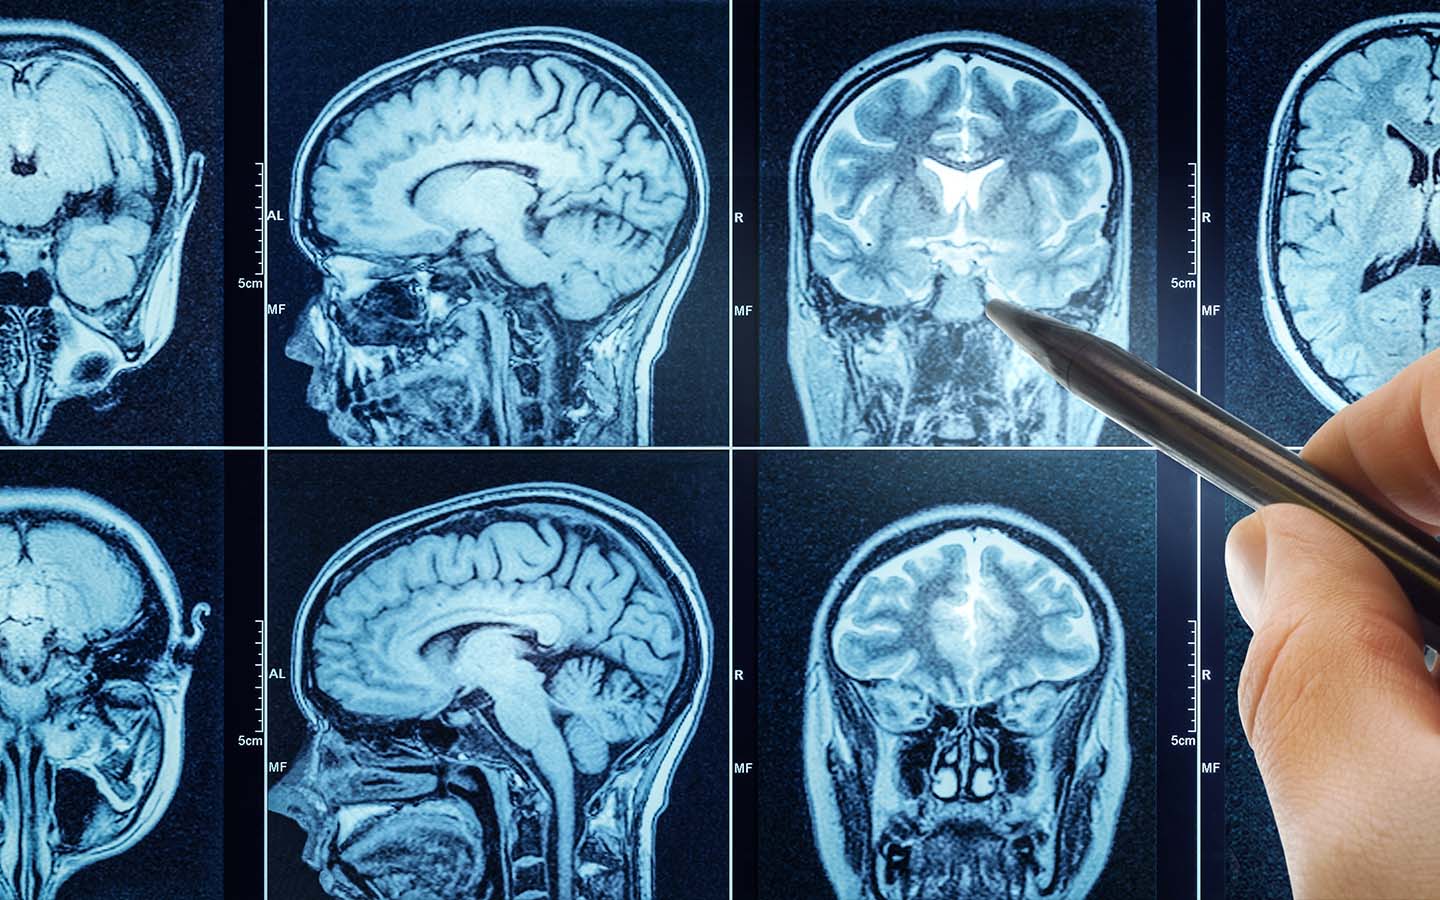

Researchers found that applying an electrical current to the frontal and parietal lobes of the brain triggers a particular brain response. When the two areas were synchronised with this weak electrical stimulation, described by one anonymous volunteer as feeling “like a warm shower or small drops of rain”, participants became more generous, more likely to offer higher amounts of money to their partner – even if doing so meant they earned less.

The study, published in the journal PLoS Biology, builds on previous research that monitored participants’ brain activity while playing the same money-sharing game. Researchers earlier identified two areas of the brain that appeared to be “talking to each other” when participants gave away more money. Synchronised activity between the frontal and parietal lobes, areas known to play a role in decision-making and in empathy, appeared when a more selfless decision was made.